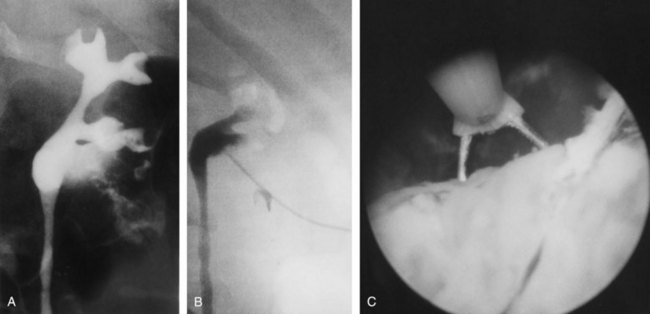

Although intravenous pyelography has been the traditional means for diagnosis of upper tract lesions, computed tomographic (CT) urography is increasingly performed today. CT is easier to perform and less labor intensive than intravenous pyelography. It also has a higher degree of accuracy in determining the presence of renal parenchymal lesions. On the other hand, small urinary filling defects (<5 mm) may be missed between the “cuts” of the traditional CT scan. More recently, CT urography has been performed to obtain a three-dimensional image of the upper tracts. This technique appears to be equal to intravenous pyelography in imaging the ureters and renal pelvis (McTavish et al, 2002). With CT urography, the sensitivity for detecting upper tract malignant disease has been reported to approach 100%, with a specificity of 60% and a negative predictive value of 100% (Caoili et al, 2002). CT urography does, however, expose the patient to higher doses of radiation.

Radiolucent filling defects, obstruction or incomplete filling of a part of the upper tract, and nonvisualization of the collecting system are the typical findings suggestive of an upper urinary tract tumor. Filling defects, which account for 50% to 75% of cases, typically require the intravenous administration of contrast material to be identified (Murphy et al, 1981; Fein and McClennan, 1986). The differential diagnosis of these defects includes blood clot, stones, overlying bowel gas, external compression, sloughed papilla, and fungus ball. Stones can be ruled out most easily by confirmation of calcification by renal ultrasonography or CT. TCCs have an average density of 46 Hounsfield units (HU) and a range of 10 to 70 HU (Lantz and Hattery, 1984). This is in contrast to an average of 100 HU seen in radiolucent uric acid stones (range, 80 to 250 HU). Thus CT can be useful in distinguishing between these two common causes of radiolucent filling defect on excretory urography or retrograde ureterography. The impact of hydronephrosis and nonvisualization for renal pelvis tumors versus ureteral tumors as indicators of a higher stage is uncertain. Nonvisualization is reported in 20% of renal pelvis tumors, only 33% of which are invasive (McCarron et al, 1983). Nonvisualization is reported in 37% to 45% of ureteral tumors and carried a 60% risk of invasion in one series (McCarron et al, 1983). In other reports there is no correlation of nonvisualization and stage (Batata and Grabstald, 1976; Anderstrom et al, 1989). Hydronephrosis with or without an associated filling defect is linked with invasion in 80% of ureteral tumors (McCarron et al, 1983; Cho et al, 2007).

Radiolucent, noncalcified lesions may require additional evaluation by retrograde urography or ureteroscopy, with or without biopsy and cytology. Overall, retrograde urography has an accuracy of 75% in diagnosis of an upper tract malignant neoplasm (Murphy et al, 1981). An incompletely filled or obstructed renal infundibulum or calyx, occurring in 10% to 30% of cases, again typically requires retrograde urography or ureteroscopy to confirm the diagnosis. Obstruction of the urinary tract is a poor prognostic sign for tumor invasion (Babaian and Johnson, 1980).

The technical advances achieved in the realm of endoscopic equipment have made the flexible and rigid ureteroscope a key part of the evaluation (and treatment) of upper urinary tract tumors. Diagnostic accuracy can be improved from approximately 75% with excretory or retrograde urography alone to 85% to 90% when it is combined with ureteroscopy (Streem et al, 1986; Blute et al, 1989). Although pyelovenous and pyelolymphatic migration has been reported with ureteroscopy, this phenomenon appears to be uncommon and should not preclude its use (Lim et al, 1993).

In some cases of upper tract tumors, percutaneous access to the renal pelvis may be required for diagnosis or treatment. In such cases, antegrade urography and uroscopy may be useful for tumor resection, biopsy, or simple visualization. Larger-caliber scopes that can be passed into the renal pelvis in this manner may be particularly helpful in resecting or debulking larger volumes of tumor in this area (Streem et al, 1986; Blute et al, 1989). One must remember, however, that tumor cell implantation in the retroperitoneum and along the nephrostomy tube tract has been reported after these procedures (Tomera et al, 1982; Huang et al, 1995).